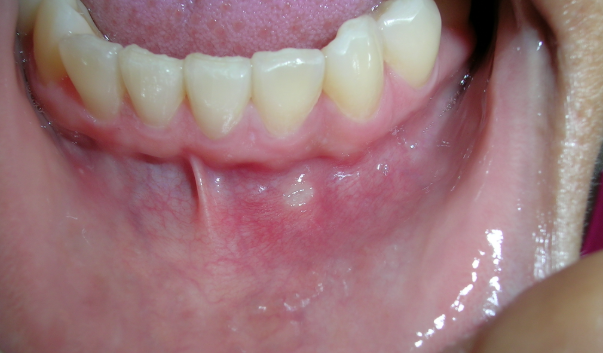

혓바늘은 누구나 일상에서 한 번쯤 경험하는 흔한 증상입니다. 작은 돌기처럼 올라와 따끔거리거나 음식 섭취 시 불편을 주며, 때로는 대화를 할 때도 신경이 쓰이곤 합니다. 많은 사람들이 혓바늘 없애는 방법을 검색하는 이유도 이런 생활 속 불편 때문입니다. 혓바늘 없애는법은 단순한 연고 사용에서부터 생활습관 관리, 병원 방문에 이르기까지 다양한 선택지가 있습니다. 이 글에서는 혓바늘 연고와 혓바늘 병원 관련 정보를 포함해, 혓바늘 없애는 방법을 폭넓게 정리해 보겠습니다.

혓바늘은 혀 표면에 국소적으로 나타나는 미세한 염증성 변화입니다. 일반적으로 피로, 수면 부족, 스트레스, 비타민 부족 등 다양한 요인과 연관이 있습니다. 저도 업무가 몰려 과로가 심했을 때 혓바늘이 자주 생겨 입안이 불편했던 경험이 있습니다. 이러한 개인적 경험에서 알 수 있듯이, 혓바늘 없애는 방법은 단순히 특정 치료에 의존하기보다 생활 전반을 점검하는 것이 기본입니다.

대부분의 혓바늘은 1~2주 내에 자연스럽게 줄어드는 경우가 많습니다. 하지만 혓바늘이 반복적으로 나타나거나, 통증이 심해 일상생활에 큰 불편을 준다면 혓바늘 병원 진료를 고려하는 것이 좋습니다. 특히 같은 위치에 반복적으로 발생하거나, 혓바늘 외에 다른 구강 내 이상 증상이 동반된다면 전문가의 확인이 필요합니다.